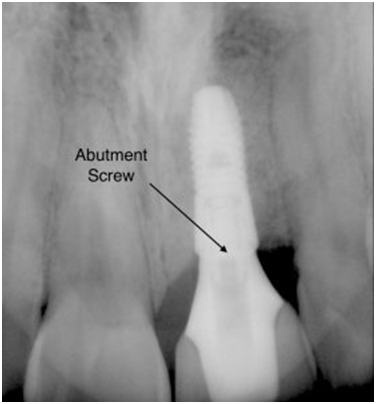

Unstable Implant Restorations

Occasionally, implant-supported crowns or bridges may need repair if components become loose or broken. Here's what to expect when repairs are needed for implant restorations:

- Loose or broken screws: If screws within the implant restoration break or loosen, they can often be replaced or retightened.

- Fractured abutments: If the abutment is fractured, the entire restoration may need to be remade.